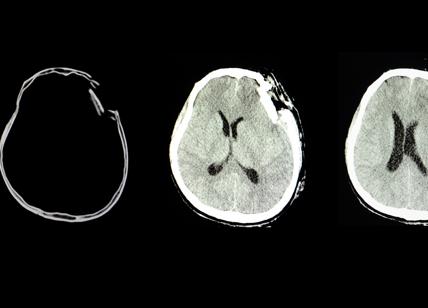

Alinity i TBI Test aiuterà gli operatori sanitari nella valutazione obiettiva dei pazienti che potrebbero aver subito un trauma cranico lieve. La maggior parte dei risultati delle scansioni con tomografia computerizzata (TC) richieste dai clinici per valutare una sospetta lesione cerebrale sono negativi. Questo esame del sangue potrà essere utilizzato come ausilio per escludere la necessità di eseguire una TC, riducendo i tempi di attesa al pronto soccorso e i costi.

Alinity i TBI Test misura due biomarcatori complementari nel plasma sanguigno e nel siero: l'idrolasi dell’ubiquitina carbossil-terminale L1 (UCHL1) e la proteina fibrillare acida della glia (GFAP), che, a concentrazioni elevate, sono strettamente correlate al danno cerebrale. I risultati del test forniscono una sensibilità del 96,7% e un valore predittivo negativo del 99,4%.

Il test è utilizzato per aiutare nella valutazione di pazienti, di età pari o superiore a 18 anni, che si presentano con sospetta lesione cerebrale traumatica lieve (punteggio della Glasgow Coma Scale 13-15) entro 12 ore dalla lesione, per aiutare a determinare la necessità di indagini strumentali più approfondite del cranio (tomografia computerizzata, TC).